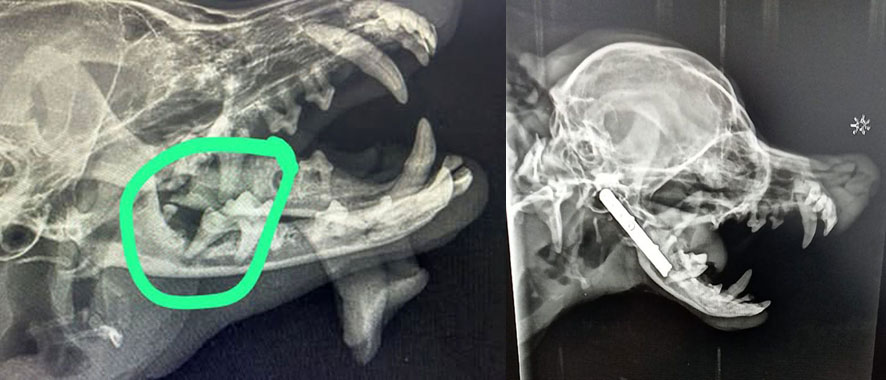

Ihr ohnehin rassetypisch sehr instabiler Kiefer war in einem schlechten Zustand. Nach einer notwendigen Zahnbehandlung kam es dann zum Schock: Der Kiefer brach.

Nina musste notoperiert werden. Ihr Kiefer wurde mit einer Titanplatte stabilisiert, damit sie überhaupt wieder schmerzfrei leben und fressen kann. Mittlerweile ist auch ihre Heilung abgeschlossen, sie ist wieder schmerzfrei, frisst und tobt durchs Leben.

Wie wunderbar, der kleine Schatz konnte in der Klinik für Kleintiere Sottrum erfolgreich operiert werden!

Wir danken dem Ärzteteam der Tierklinik für seine hervorragende Arbeit. Die Ärzte waren über den Zustand des Kiefers entsetzt. Sie sagten: Die erste OP der doppelten Fraktur des Unterkiefers auf Ibiza, war so schlecht gemacht, dass nach der OP dem kleinen Hündchen auf einer Seite permanent das Zünglein aus dem Mäulchen hing und es wurde so unsauber gearbeitet, dass sich im ganzen Kiefer Eiter bildete und die andauernde Entzündung den Kieferknochen zersetzt hat. Auch die mehr als zweimonatige Nachbehandlung damals brachte keine Besserung. Schließen des Mäulchens war nicht mehr möglich. Die Ärzte in Deutschland waren gezwungen den halben Unterkiefer zu entfernen. Wenn in 2 Wochen die Entzündungen ausgeheilt sind, ist eine weitere OP nötig, bei der dann eine Lippenplastik gemacht wird, damit Mausi in Zukunft wieder besser fressen und das Mäulchen schließen kann.

Eine Freundin von TINI erzählte uns von einem kleinen Hündchen, das dringend gerettet werden sollte. Wir fuhren sofort los und lernten den Besitzer kennen. Es war ein Chihuahuazüchter der auch große Hunde verkauft. Er kam uns mit einem kleine Wesen auf dem Arm entgegen. Mit Entsetzen blickten wir auf das Gesichtchen: Ein Auge blind und das Zünglein hängt auf einer Seite raus, weil der Kiefer gebrochen war. Die Ursache war der Biss von einem seiner großen Hunde. Trotz damals ärztlicher Versorgung vom Züchter mit OP beim Tierarzt auf Ibiza war das Auge nicht zu retten und der Kiefer ist nicht korrekt zusammen gewachsen. Eine Fachklinik auf Ibiza gibt es nicht. In Deutschland gibt es so eine Klinik und wir haben das Glück für Mausi eine Pflegemama gefunden zu haben, die Mausi zu sich nimmt, damit sie in dieser Klinik  noch einmal operiert werden kann. So kann man wahrscheinlich ein jahrelanges Martyrium vermeiden. Die Kleine wird trotz allem sehr viel Freude machen, sie ist ein Herzenshündchen. Liebe TINI Freunde, ohne Ihre Unterstützung können wir die auf uns zukommenden Kosten nicht stemmen. Mit jeder Spende können wir Mausis Leben verbessern. Dafür danken wir Ihnen von Herzen!